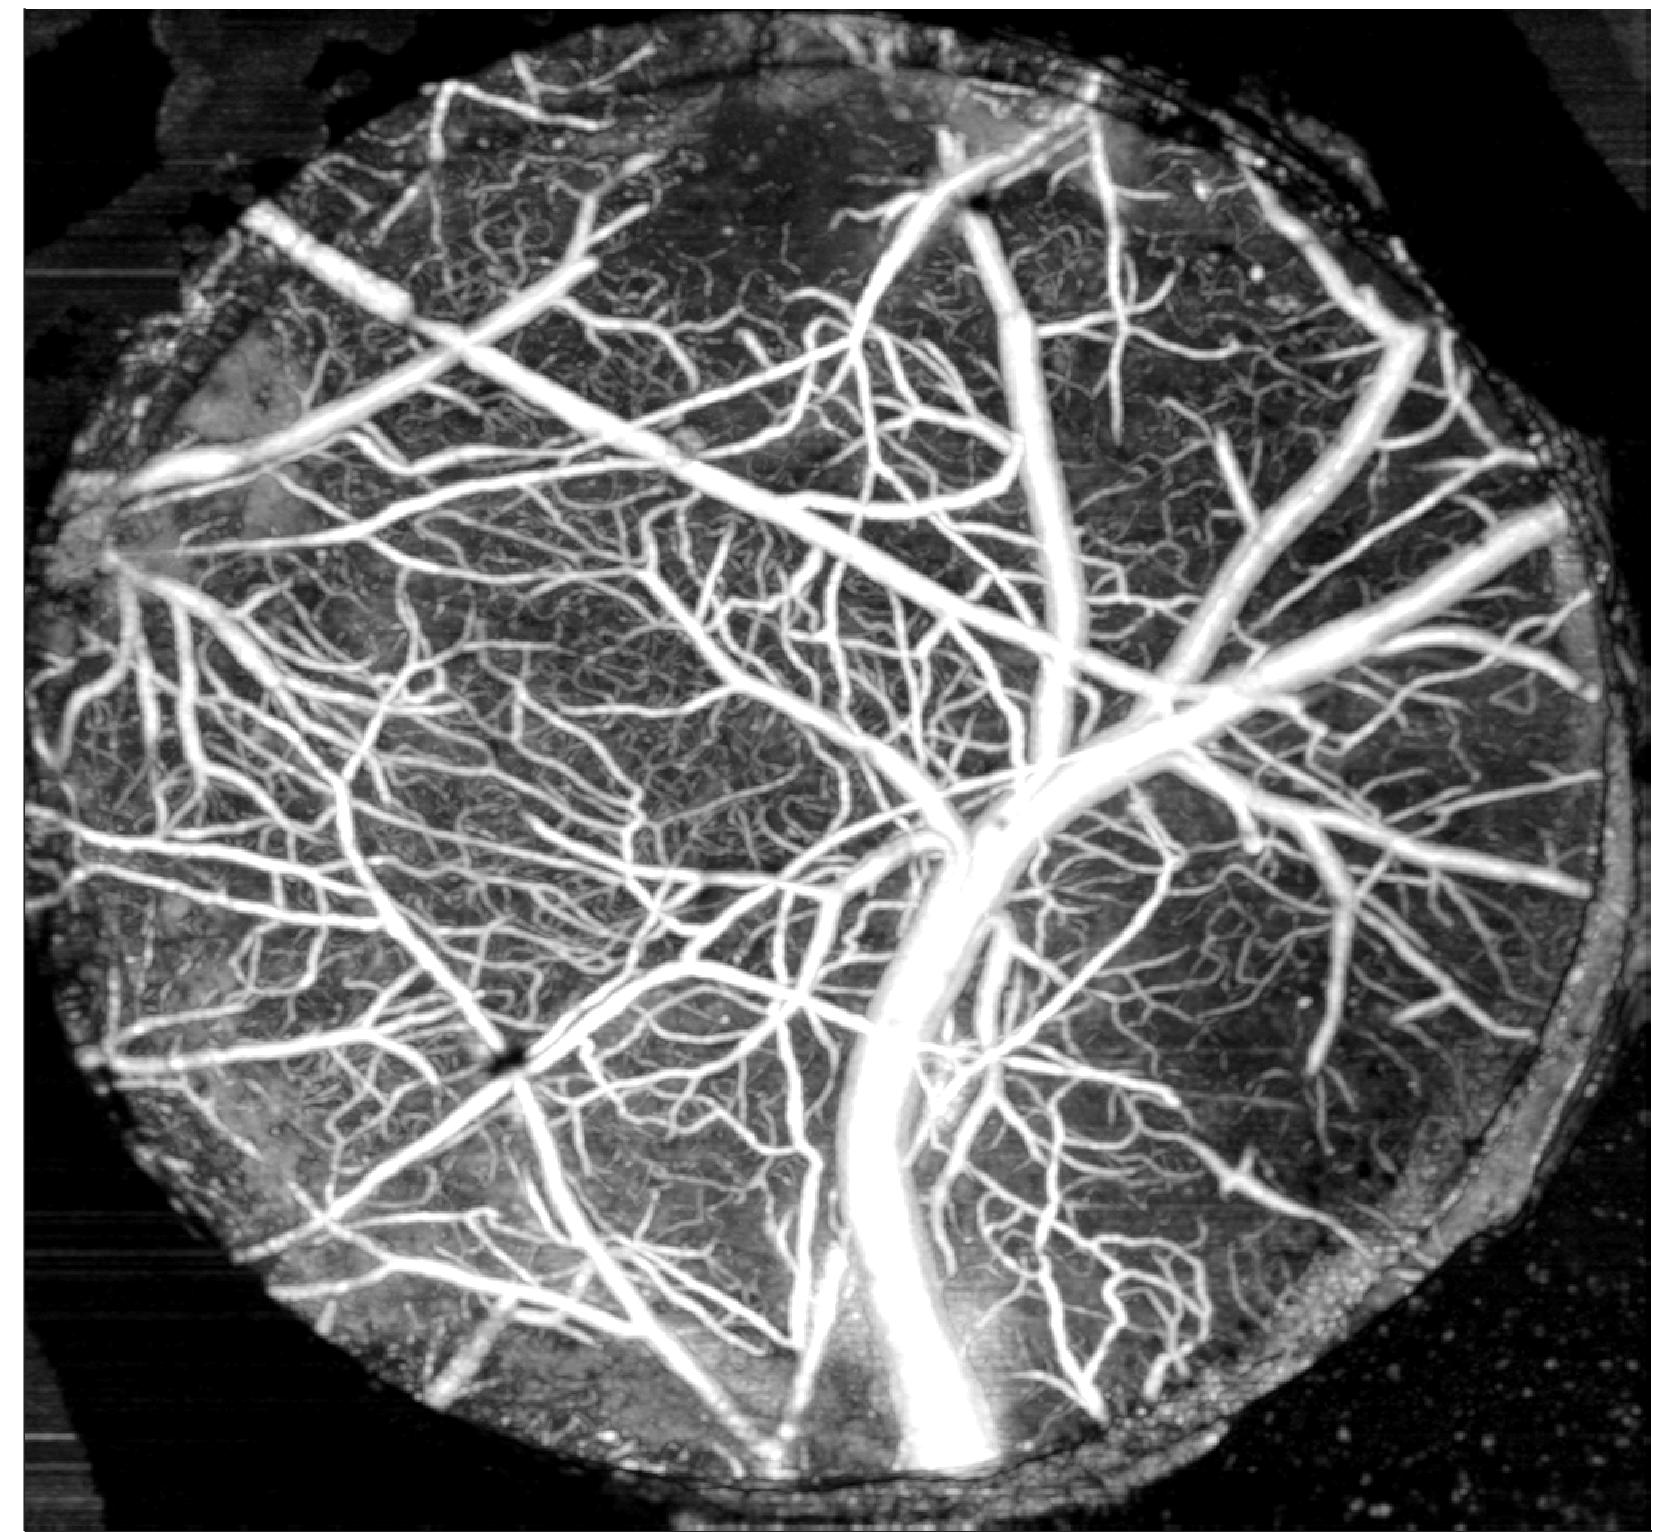

視網膜成像(如下圖):

圖注:SD-OCT在小鼠視網膜成像中的應用示例,展示了多層結構分辨與定量測量能力。